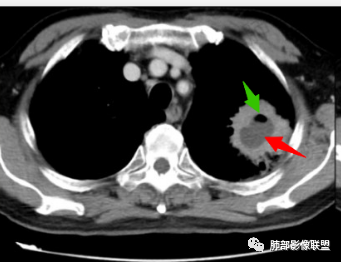

厚壁空洞,内壁光滑,内部液化坏死

厚壁环形强化明显

鳞癌,老年男性支持,影像不太支持,空洞壁光整,没有壁结节,坏死太彻底,鳞癌湖泊样坏死有过渡区。

3.CT表现:肺脓肿可呈结节状或团块状,有时呈不规则形,气道来源肺脓肿常单发,血行来源常多发,边缘模糊,部分病灶周围可见片状肺实变及磨玻璃影;病灶中央为液化坏死区,若脓肿与支气管相通,脓液排出可形成空洞,空洞内可形成液平;急性肺脓肿内壁多不规则;慢性肺脓肿洞壁较厚,一般不规则或形成多房空洞:CT增强扫描空洞壁可见强化,空洞壁为纤维肉芽组织,呈典型的环形强化;慢性肺脓肿周围可有较广泛的纤维索条影,可伴支气管扩张、肺气肿或胸膜增厚表现。

何家伟老师的精彩分析本例指向慢性肺脓肿主要有以下几点:1.患者病史长,白细胞不高,无发热,病程中有浓痰;2.慢性肺脓肿多为厚壁空洞,邻近肺野可见慢性肺炎、长纤维索条影;3.本例厚壁空洞,明显均匀环形强化,外壁见不规则棘突,未见明显分叶毛刺;内壁光滑,有完整强化环,无凹凸不平及壁结节等;4.空洞厚壁中可见血管穿行,未见破坏侵犯征象;5.邻近胸膜呈糊墙改变,胸膜下脂肪间隙清晰,未见侵犯,倾向炎性改变;6.空洞内可见液化坏死及气体,非凝固性坏死、干酪性坏死;7.纵隔及肺门未见肿大淋巴结。